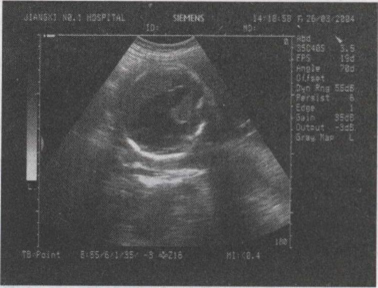

33.一孕妇,孕28周,根据胎儿头部B超声像图,最可能的诊断为()